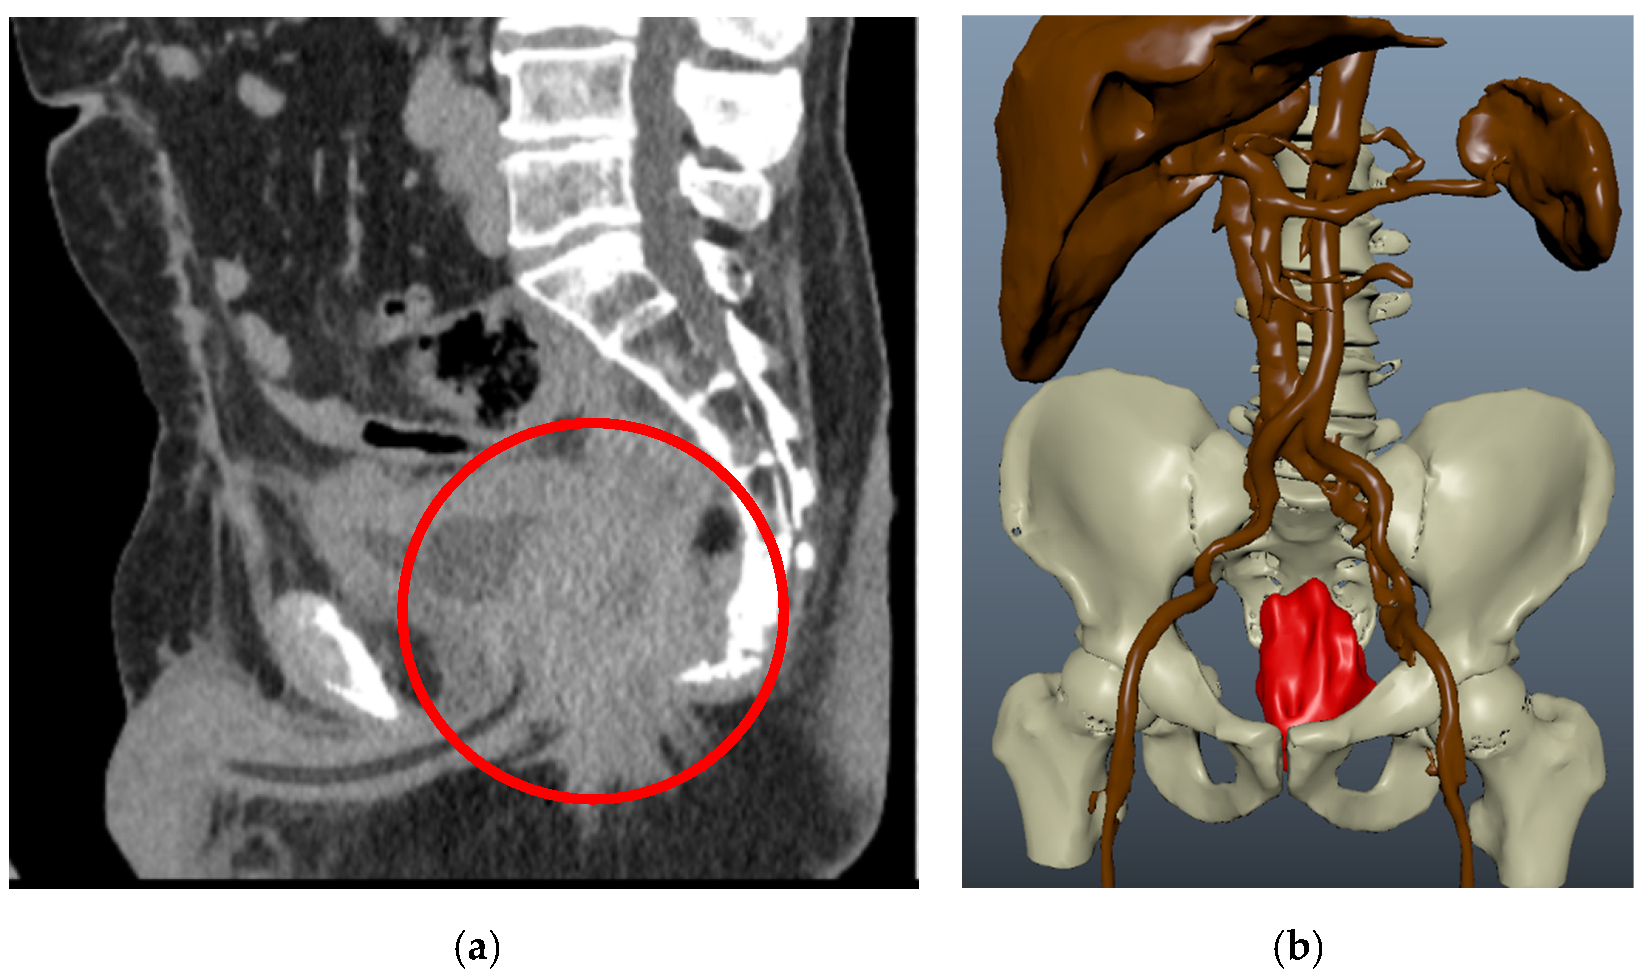

| 3 | Ovarian cancer T3cNxM1 IVa st.1 | Combined cytoreductive (initially optimal) operation: posterior supralevator evisceration of the small pelvis. Resection of the right dome of the diaphragm. Resection of the greater and lesser omentum. Obstructive resection of the sigmoid colon. Total peritonectomy. Cholecystectomy, splenectomy, appendectomy. Resection of the right ureter (Figure 8). | 390 |